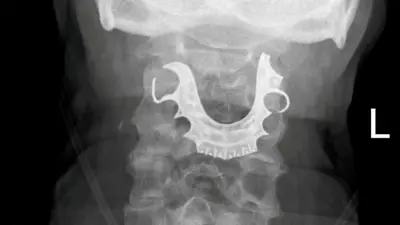

La dentadura postiza de un hombre de 72 años se encontró alojada en su garganta ocho días después de la cirugía, lo que provocó complicaciones y lo obligó a someterse posteriormente a un procedimiento de emergencia.

El hombre, un electricista retirado, se sometió a una "operación menor" para extraer un bulto benigno en su estómago cuando sus dentaduras postizas, una placa de techo de metal con tres dientes postizos, se desprendieron, informó SWNS, citando informes de casos de BMJ. SWNS no dijo de dónde es el hombre o dónde se realizó la cirugía.

Pero no mejoró y fue ingresado en el hospital solo dos días después. Los médicos le dijeron a los médicos que "vieron un objeto semicircular sobre sus cuerdas vocales", según SWNS.